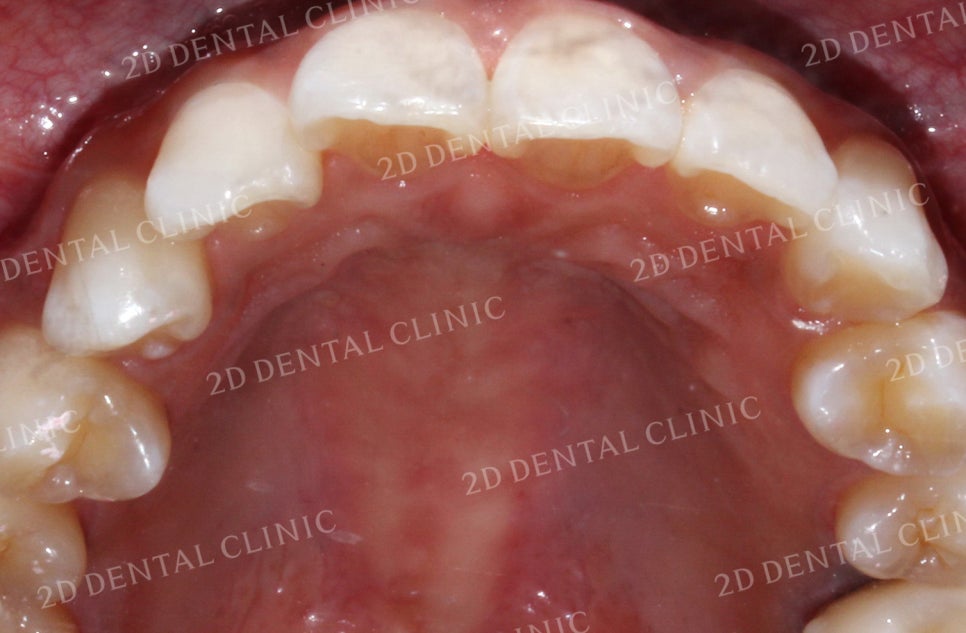

상악의 설측면 사진입니다.

상악의 경우 앞니와 송곳니가

미세하게 총생이 있어

전치부의 치아들이 전반적으로

삐뚤어진 느낌입니다.